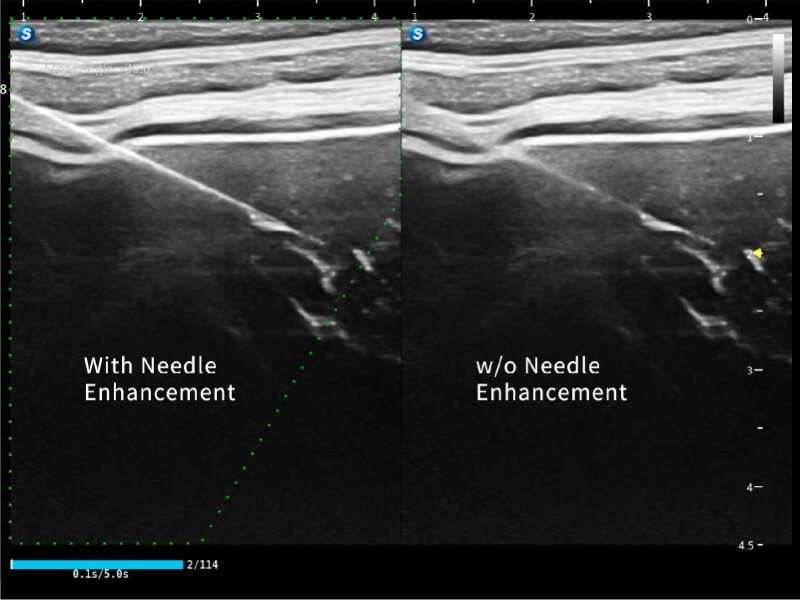

作为开立医疗全新打造的高端床旁笔记本超声,E11不仅具备卓越的图像质量,同时搭载全面高效的自动测量工具,助力医生实现更快速、更精准的床旁诊断。

E11搭载了丰富的自动化测量工具,以及专为POC科室定制的高级功能;同时配备了为急诊医师量身打造的 SonoFast急重症超声流程,以帮助临床医生最大限度的提升工作效率